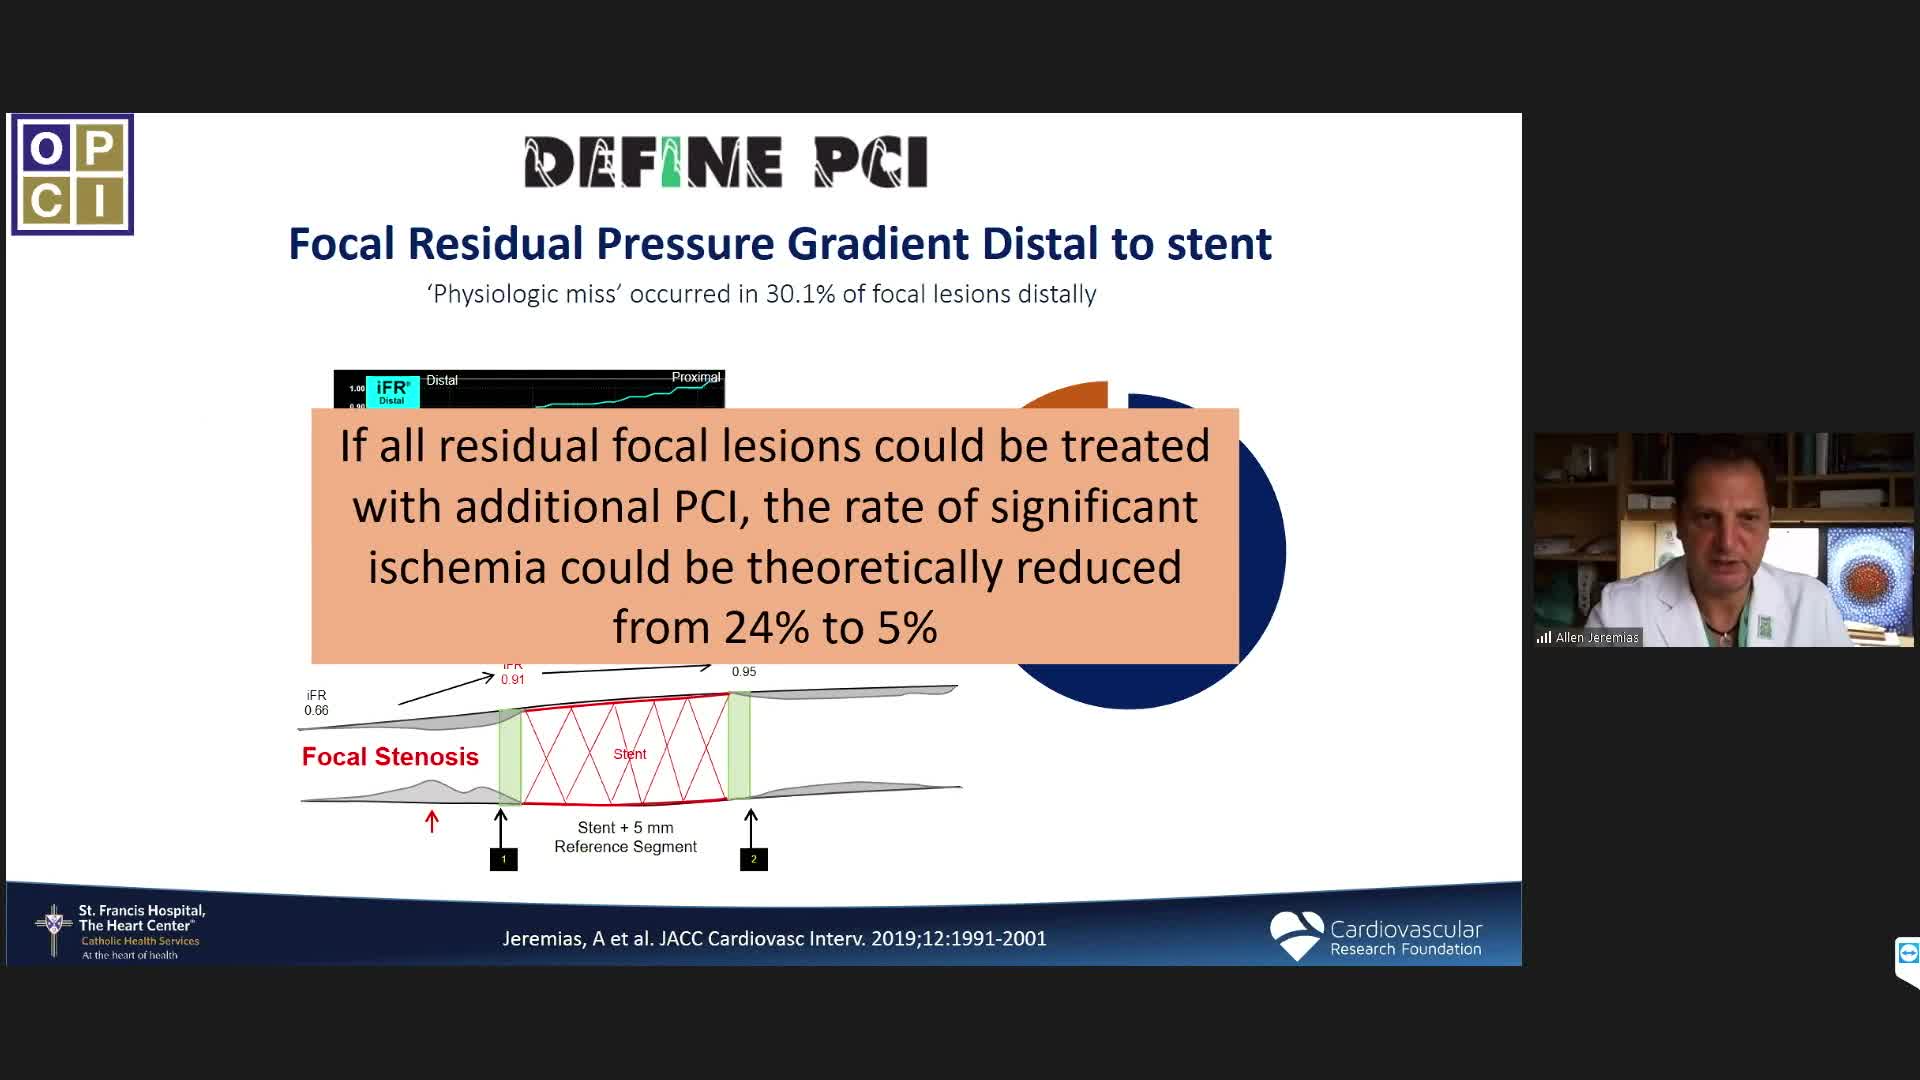

Essential steps for physiology-based PCI planning and guidance - Dr Allen Jeremias